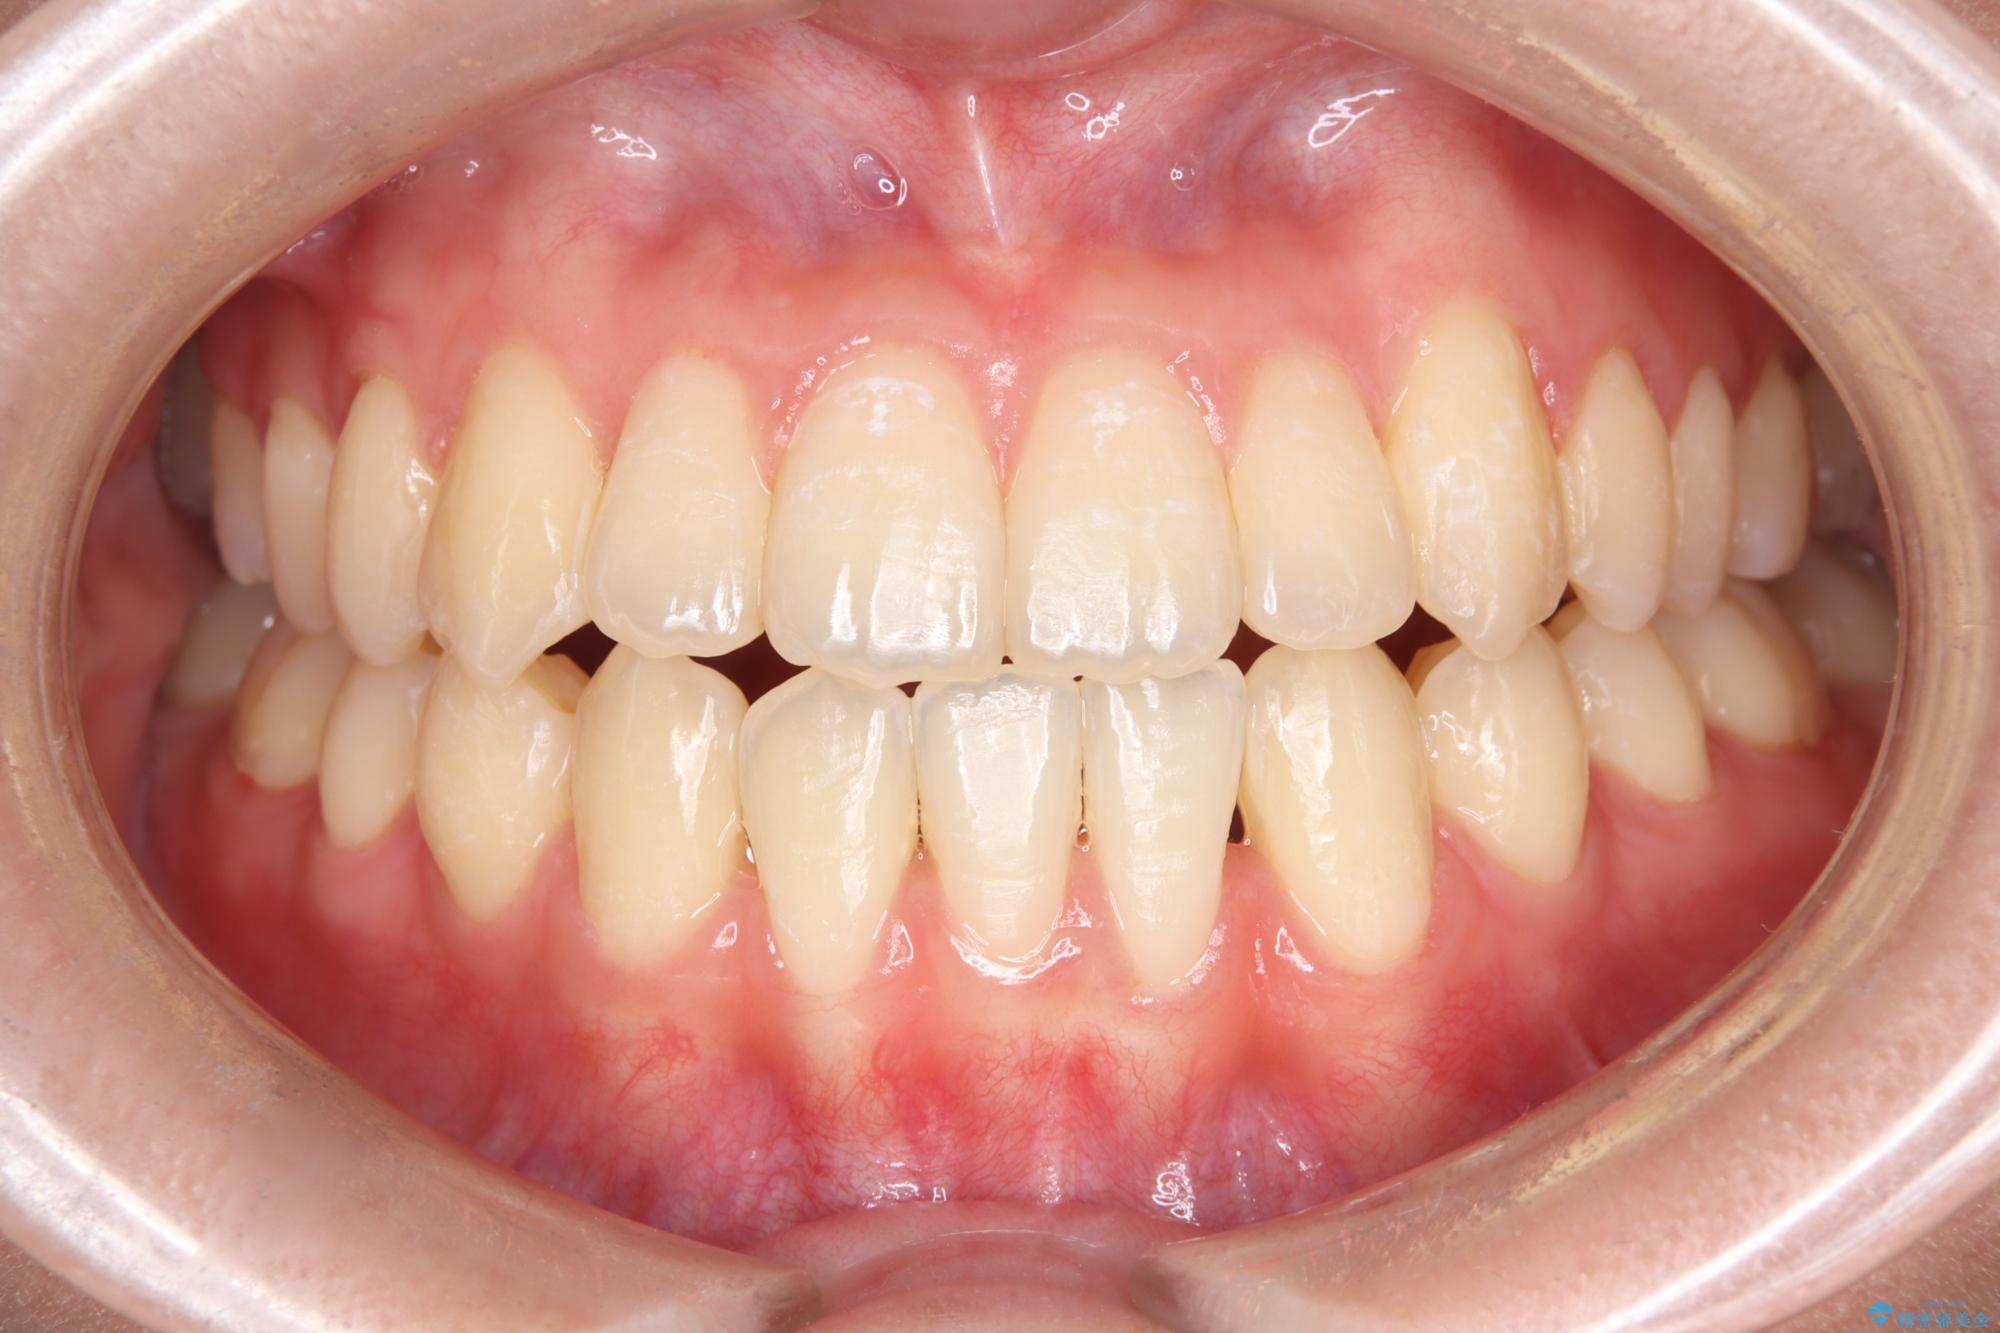

転院という不安な状況にある患者様のストレスを最小限に抑えつつ、歯の健康を最優先にした処置を行いました。

装置の変更と歯肉への配慮: ワイヤー矯正は歯の根(歯根)を平行に移動させる「歯体移動」を得意としています。本症例では、歯肉退縮を防ぐために、歯の傾きを精密にコントロールしながら抜歯スペースを閉じる必要がありました。ワイヤー装置を用いることで、インビザラインでは難しくなっていた三次元的な細かい調整を可能にしました。